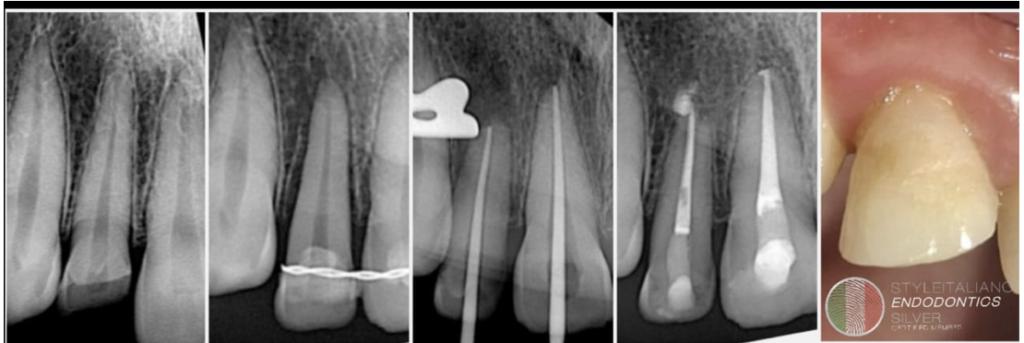

Surgical Extrusion of upper lateral incisor with oblique fracture

A 20-year-old male patient reported to our clinic with a history of trauma involving the maxillary right central and lateral incisors. Clinical examination revealed an oblique crown fracture of the right lateral incisor, with the fracture line extending subgingivally. Considering the extent and position of the fracture, surgical extrusion of the affected tooth was planned as the treatment of choice.

Fig. 1

Pre op radiograph showing fractured right lateral incisor.

Fig. 2

Tooth was carefully extruded with the help of luxators and forceps about 4mm inside the socket. And splinted with the help of wire.

Fig. 3

Splint was removed after two weeks.. Patient was advised to come for endodontic treatment after two weeks.